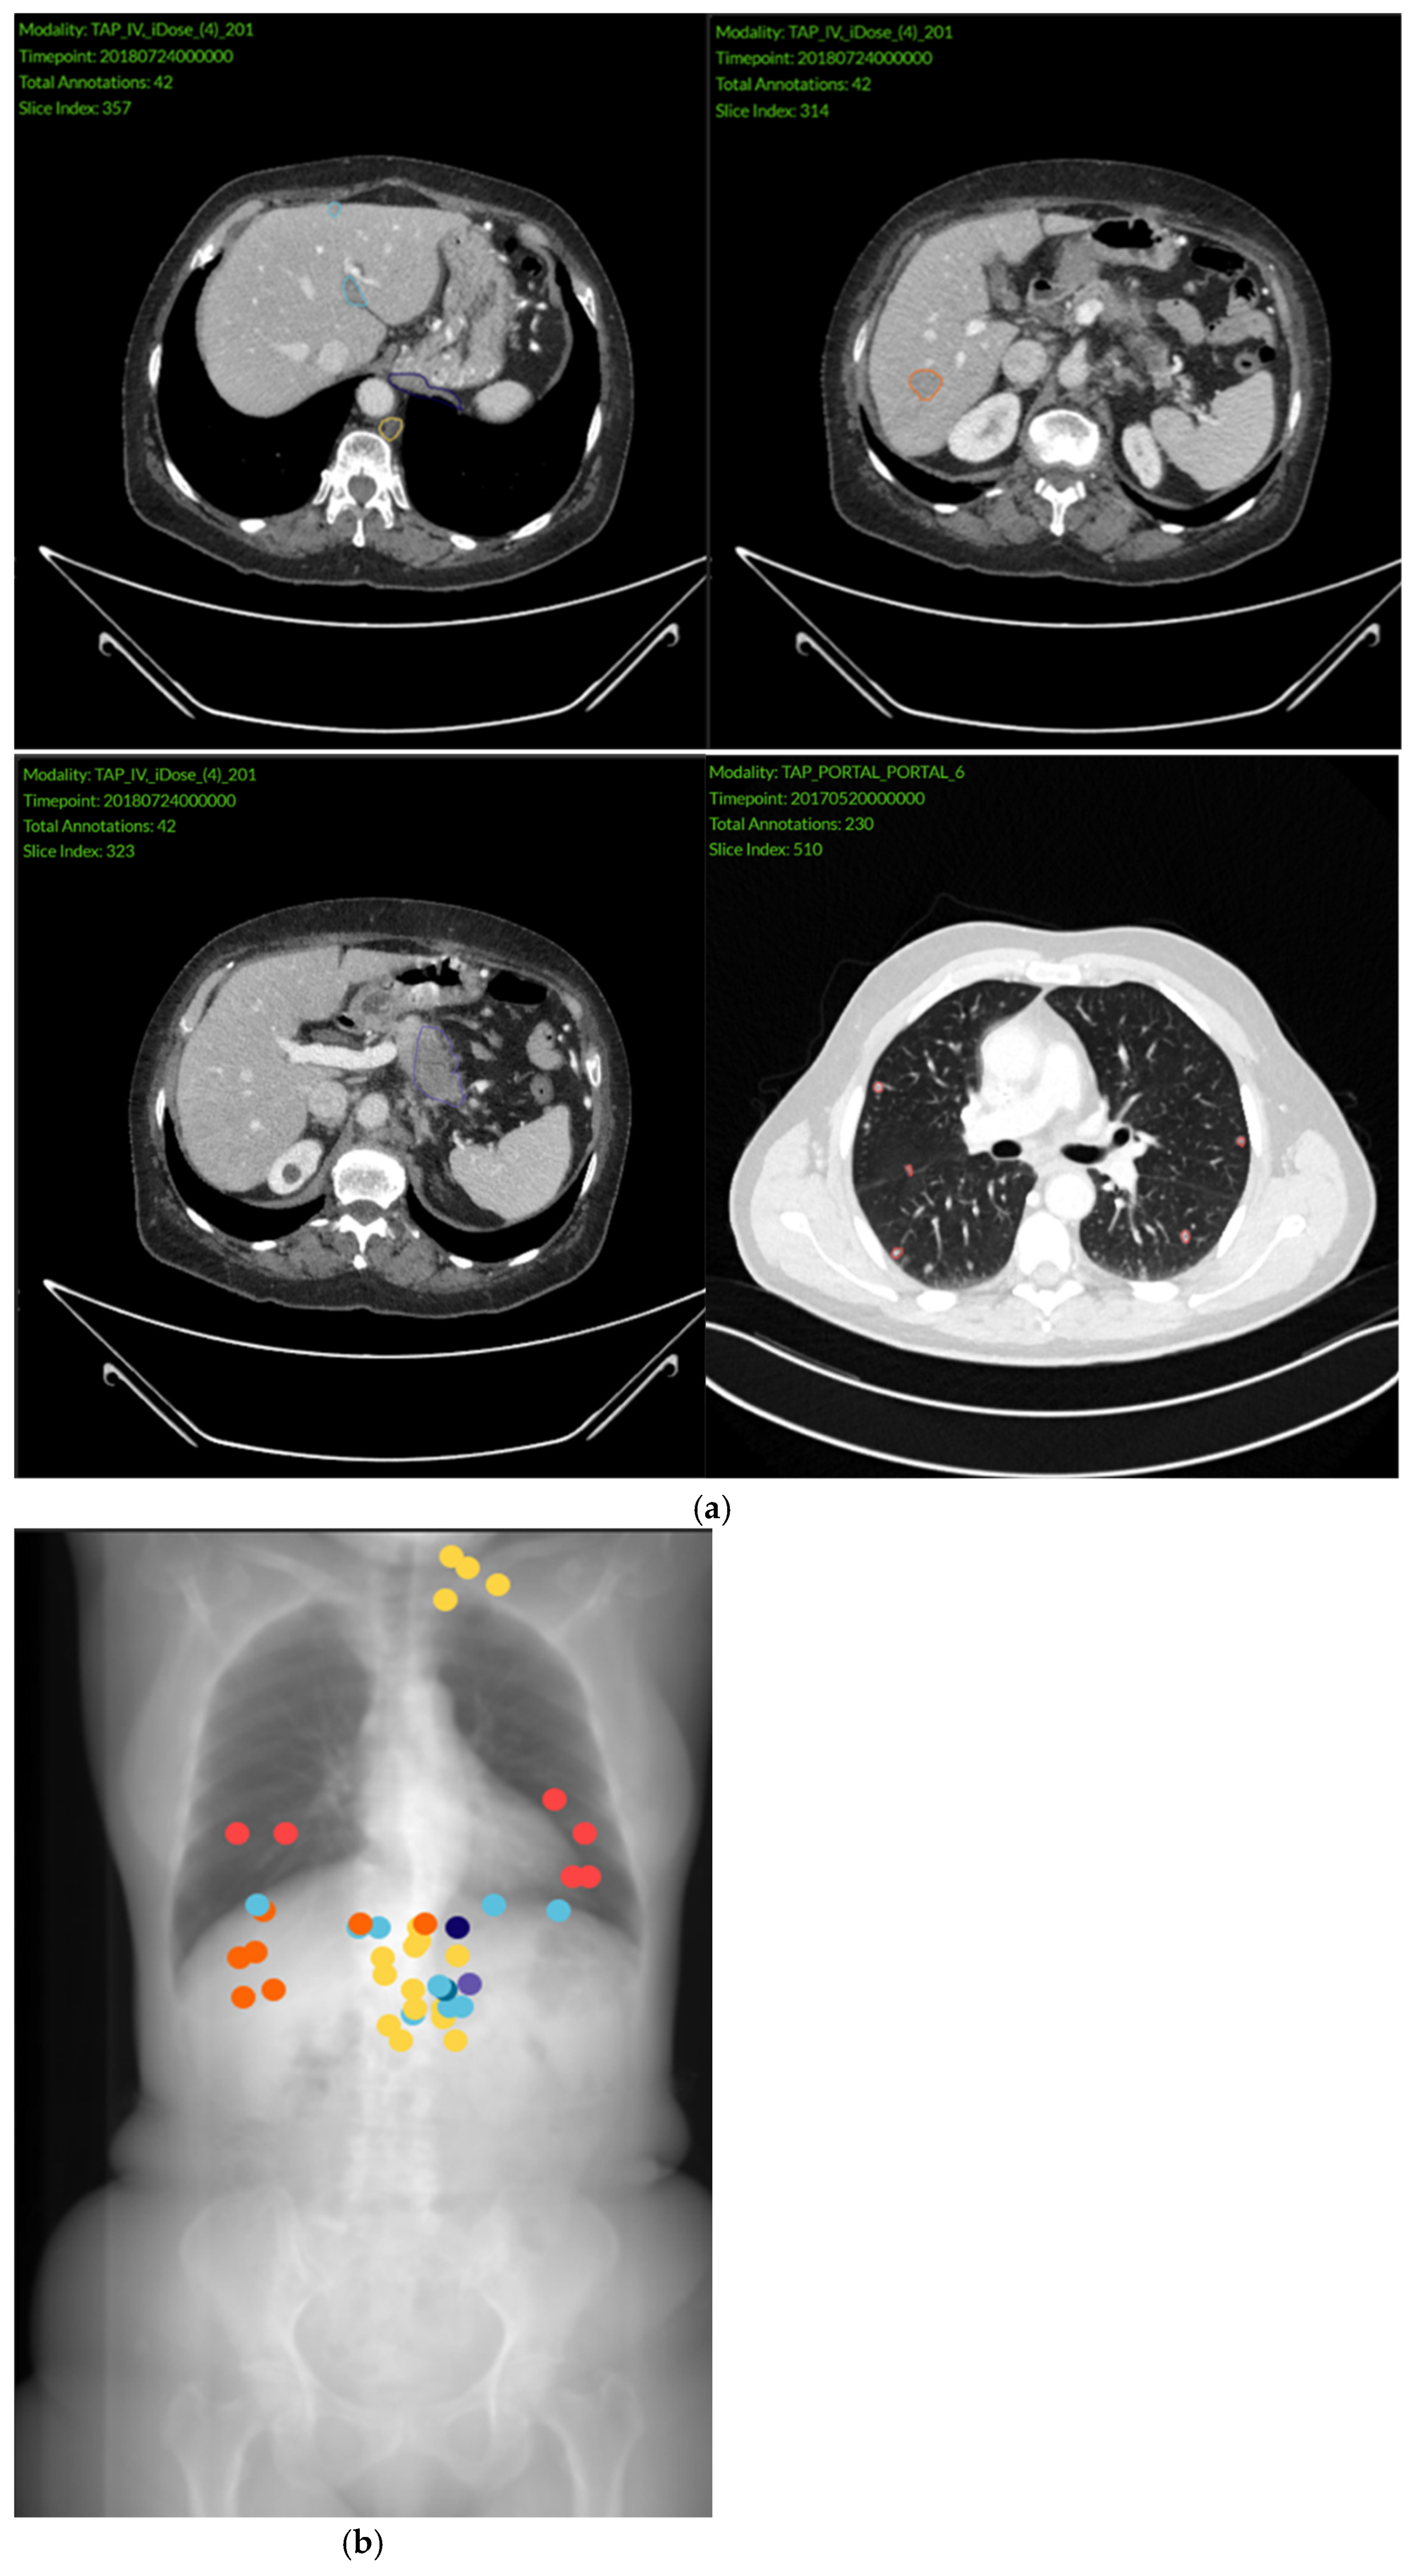

2.2. Imaging Analysis

3.2. Imaging Findings